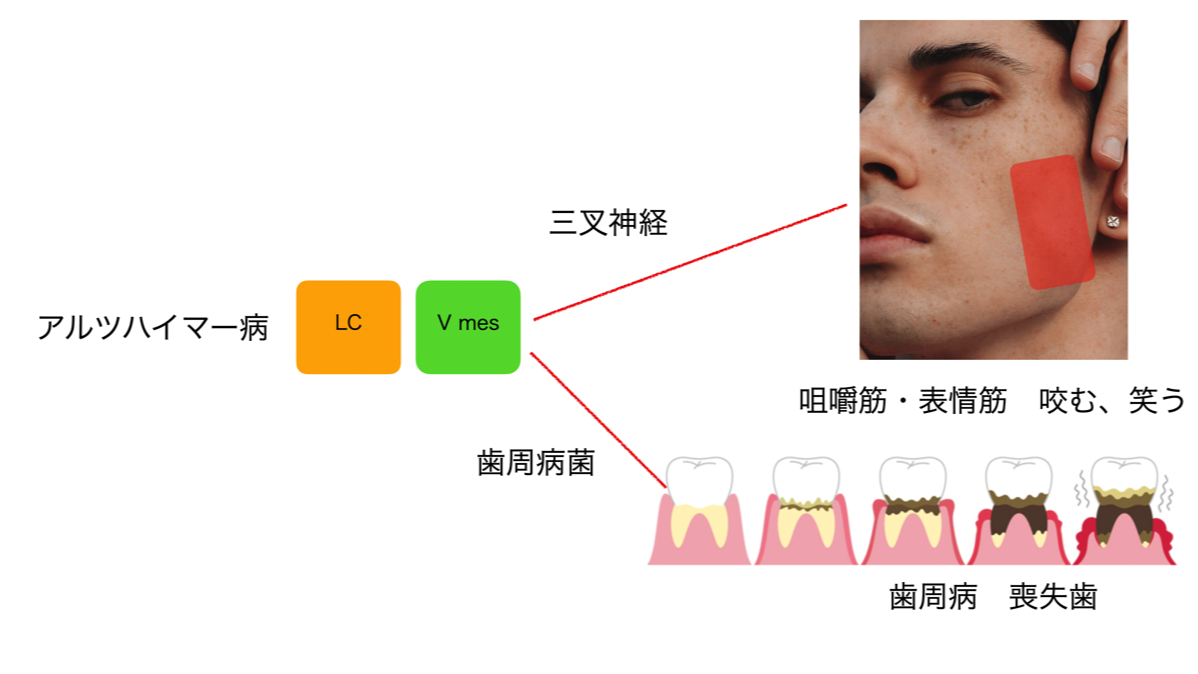

アルツハイマー型認知症と歯科疾患

アルツハイマー病は長い年月をかけて脳に異常物質が蓄積して発症します。この異常物質が最初に蓄積する部位は、脳の青斑核 (LC) という部位です。

この青斑核のすぐ外側に三叉神経中脳路核 (V mes) が有り、お互いに連絡を取り合っています。

三叉神経は顔や口、歯や歯肉に広く分布する神経です。例えば歯の痛みは、痛みの刺激がこの三叉神経の神経線維を通って脳に情報が伝わることで異常が検知できます。

ところで、歯の周りには歯根膜と呼ばれる薄い靭帯があり歯と骨をつなげています。

この歯根膜内に神経の受容体があるのですが、ここからも神経線維が V mes まで伸びています。猫の観察ではV mesのうち20%が、猿では10-15%が歯根膜から伸びる神経線維で占められていました。

歯を抜くとこの神経線維が失われ、V mesの内部でも5日以内に変性して神経が消えていました。

また、歯周組織や歯の神経(歯髄)の損傷や感染で、V mesだけではなくLCまで悪影響が想像されています。

咀嚼筋にも受容体があり、こちらからもV mesまで神経線維が伸びています。

さらに咬んだ力の感覚はV mes に留まらず、前頭、視床、辺縁系など脳全体に伝わります。

咬むのを止めてしまうと、脳への血液の供給も悪くなります。

動物実験では、奥歯を抜歯すると12週後には、記憶に関わる脳の領域で明らかな変化が認められました。記憶領域の海馬というところで新しい神経細胞が減ってしまい記憶の低下がみられました。

咀嚼の障害で脳に異常物質も溜まり、広範な脳の炎症の引き金になるようです。

歯周病菌の中には、重症の歯周病を引き起こすレッドコンプレックスと呼ばれるグループの菌がいます。

P. gingivalis菌とアルツハイマー病に関わりがあるとされています。

T. denticola菌もアルツハイマー病に関わりがあり、三叉神経の神経線維内を這って脳の中に侵入していきます。実際、アルツハイマー病の方の脳でT.denticolaが見つかっています。ちなみにTはトレポネーマ菌のTで、T. pallidumは梅毒の病原菌です。

この青斑核のすぐ外側に三叉神経中脳路核 (V mes) が有り、お互いに連絡を取り合っています。

三叉神経は顔や口、歯や歯肉に広く分布する神経です。例えば歯の痛みは、痛みの刺激がこの三叉神経の神経線維を通って脳に情報が伝わることで異常が検知できます。

ところで、歯の周りには歯根膜と呼ばれる薄い靭帯があり歯と骨をつなげています。

この歯根膜内に神経の受容体があるのですが、ここからも神経線維が V mes まで伸びています。猫の観察ではV mesのうち20%が、猿では10-15%が歯根膜から伸びる神経線維で占められていました。

歯を抜くとこの神経線維が失われ、V mesの内部でも5日以内に変性して神経が消えていました。

また、歯周組織や歯の神経(歯髄)の損傷や感染で、V mesだけではなくLCまで悪影響が想像されています。

咀嚼筋にも受容体があり、こちらからもV mesまで神経線維が伸びています。

さらに咬んだ力の感覚はV mes に留まらず、前頭、視床、辺縁系など脳全体に伝わります。

咬むのを止めてしまうと、脳への血液の供給も悪くなります。

動物実験では、奥歯を抜歯すると12週後には、記憶に関わる脳の領域で明らかな変化が認められました。記憶領域の海馬というところで新しい神経細胞が減ってしまい記憶の低下がみられました。

咀嚼の障害で脳に異常物質も溜まり、広範な脳の炎症の引き金になるようです。

歯周病菌の中には、重症の歯周病を引き起こすレッドコンプレックスと呼ばれるグループの菌がいます。

P. gingivalis菌とアルツハイマー病に関わりがあるとされています。

T. denticola菌もアルツハイマー病に関わりがあり、三叉神経の神経線維内を這って脳の中に侵入していきます。実際、アルツハイマー病の方の脳でT.denticolaが見つかっています。ちなみにTはトレポネーマ菌のTで、T. pallidumは梅毒の病原菌です。